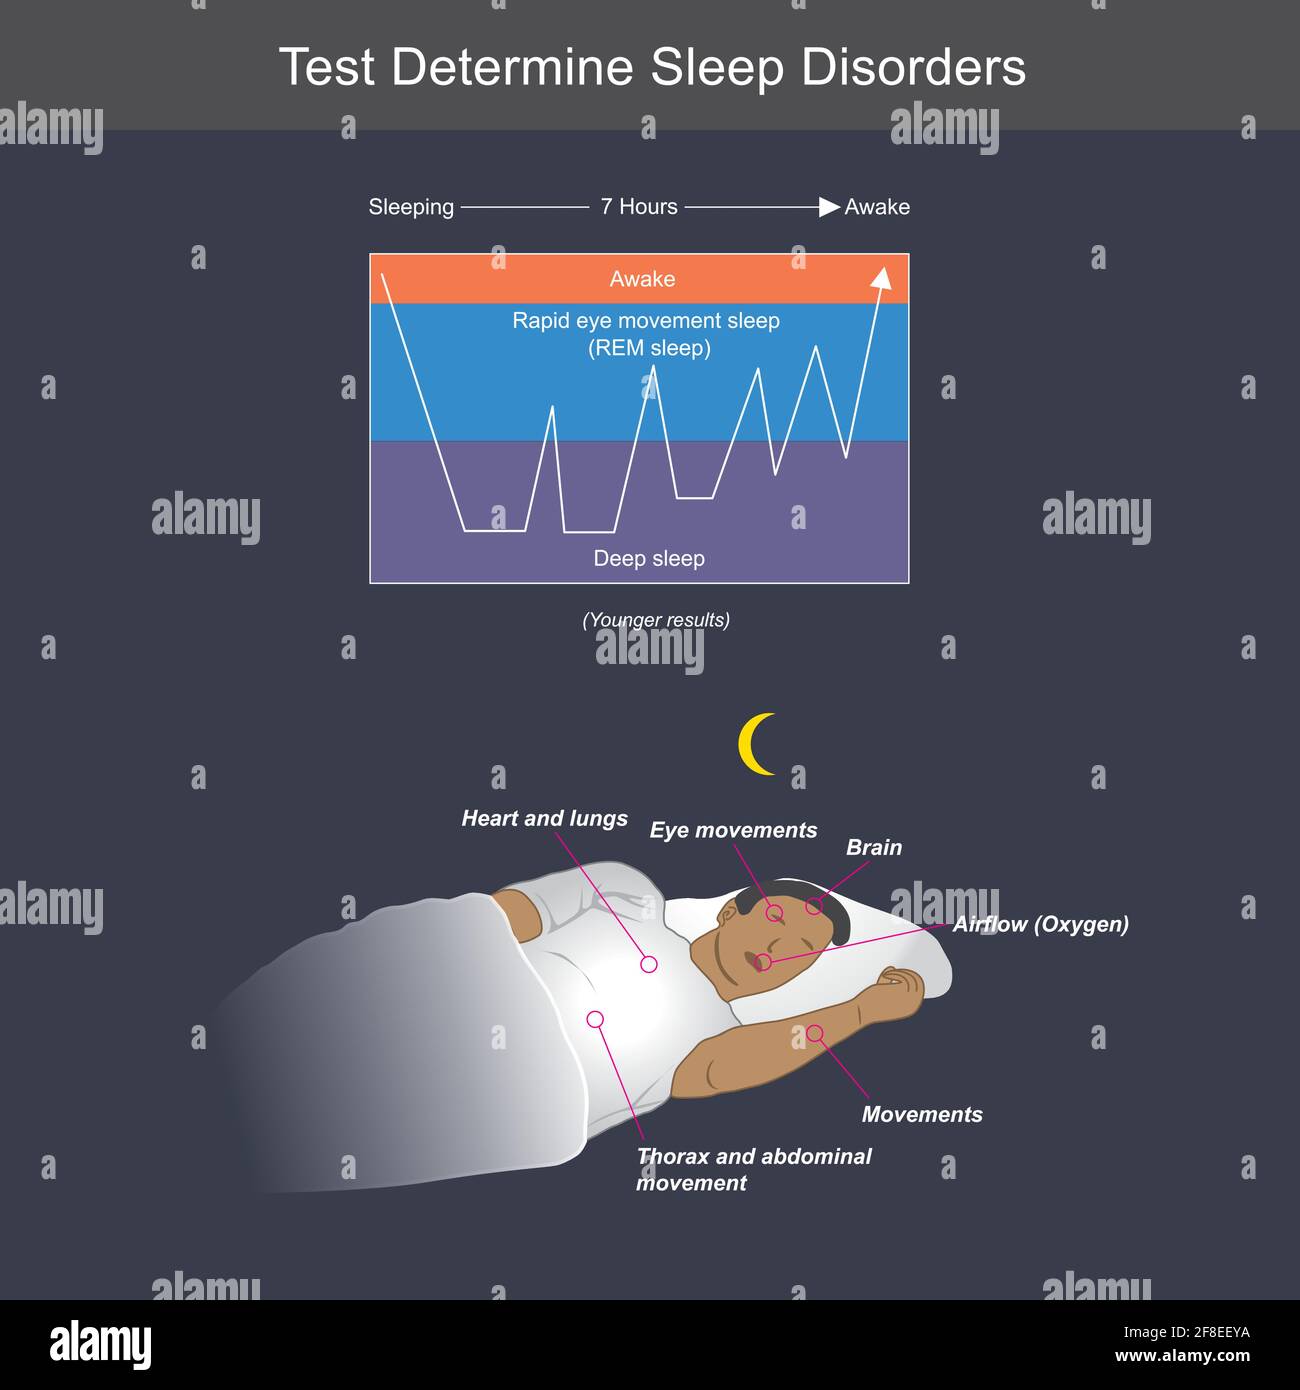

Test determinare i disturbi di sospensione. Illustrazione che mostra UN uomo che ha finito di dormire per tutta la notte, con il sistema della carrozzeria ancora normale. Illustrazione Vettorialehttps://www.alamy.it/image-license-details/?v=1https://www.alamy.it/test-determinare-i-disturbi-di-sospensione-illustrazione-che-mostra-un-uomo-che-ha-finito-di-dormire-per-tutta-la-notte-con-il-sistema-della-carrozzeria-ancora-normale-image418285150.html

Test determinare i disturbi di sospensione. Illustrazione che mostra UN uomo che ha finito di dormire per tutta la notte, con il sistema della carrozzeria ancora normale. Illustrazione Vettorialehttps://www.alamy.it/image-license-details/?v=1https://www.alamy.it/test-determinare-i-disturbi-di-sospensione-illustrazione-che-mostra-un-uomo-che-ha-finito-di-dormire-per-tutta-la-notte-con-il-sistema-della-carrozzeria-ancora-normale-image418285150.htmlRF2F8EEYA–Test determinare i disturbi di sospensione. Illustrazione che mostra UN uomo che ha finito di dormire per tutta la notte, con il sistema della carrozzeria ancora normale.